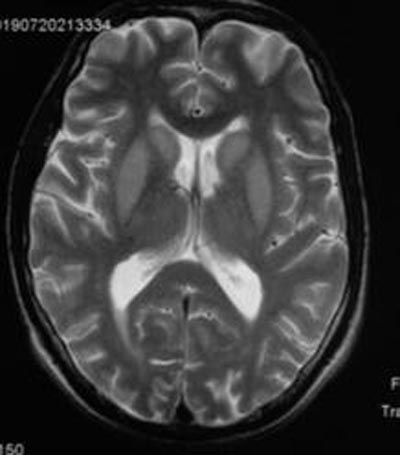

患者男性,42岁,因“嗜睡1月余,阵发性面部抽搐1天”入院。患者既往在当地因“食管癌”行手术及放化疗,自诉已恢复良好。患者MR片显示双侧基底节区对称性T2WI、FLAIR系列高信号,DWI序列提示弥散轻度受限。入院当天离子五项显示钾离子、钠离子、氯离子、镁离子均降低,其中钠离子为131.4mmol/L。遂询问患者家属相关病史,患者于1月前出现嗜睡,于当地医院对症治疗(补充电解质)稍好转,随后出现阵发性面部抽搐,为进一步治疗转至我院。综合病史及实验室检查,高度提示脑桥外髓鞘溶解(extrapontine myelinolysis , EPM)。

CPM 常累及脑桥基底部,呈现对称性类似"蝙蝠样"病灶,其中髓鞘溶解,而神经元突相对完好,从中缝向两侧发展。而EPM多累及基底节、皮质、小脑等脑桥外结构[2]。发病初期CT检查对本病可无异常发现。故磁共振成像 (MRI) 对诊断ODS 起到重要作用,尤其是MR弥散加权成像 (diffusion weighted imaging , DWI) 及表观扩散系数 (apparent diffusion coefficient , ADC)使得 ODS 的早期诊断成为可能。

T2WI